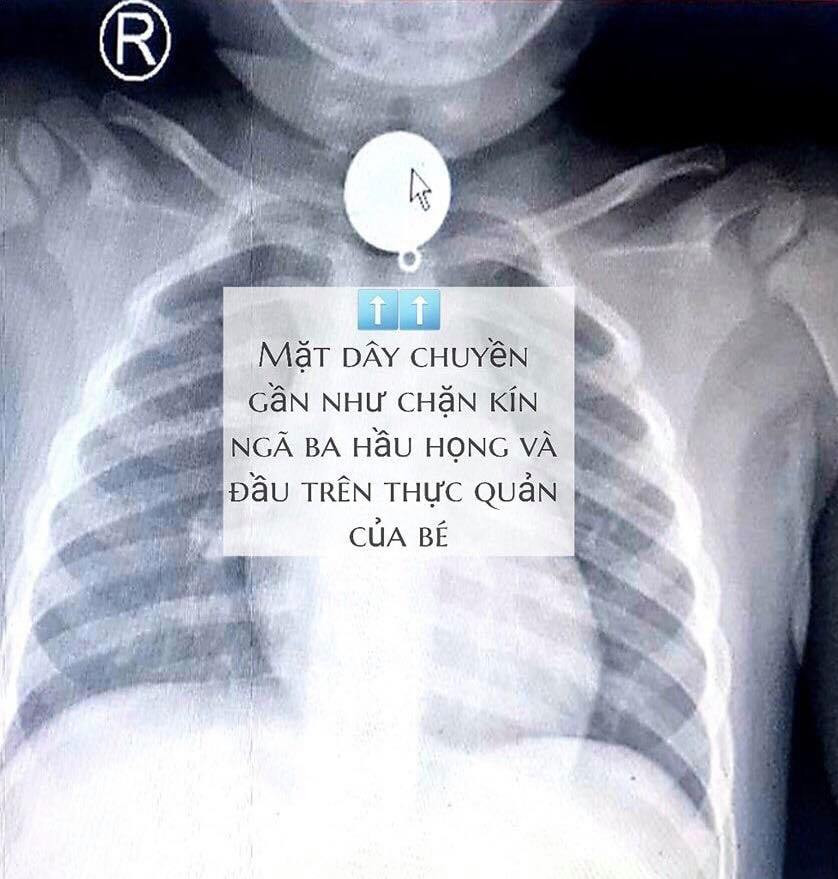

TPO - Bệnh nhi được đưa đến bệnh viện trong tình trạng khó thở. Kết quả chụp X-Quang cho thấy có một dị vật mắc trong cổ bé rất to, chiếm hết lòng đầu trên thực quản, gần ngay ngã 3 thông với đường thở.

Hình ảnh chụp X-quang cho thấy dị vật chặn cứng đầu trên thực quản. ẢNh: BVCC

Tại Bệnh viện, sau khi hội chẩn xác định dị vật mắc trong cổ bé rất to, hình tròn nằm chiếm hết lòng đầu trên thực quản, gần ngay ngã ba thông với đường thở, các bác sĩ nhận định khả năng dị vật gây trầy, rách thực quản, hay hóc ngược vào đường thở rất cao nếu xử trí không khéo. Sau đó, e-kip nội soi trực tai mũi họng do BSCK2 Trần Thiện Nhơn quyết định tiến hành gây mê nhẹ nhàng, dùng ống soi gắp dị vật ra khỏi thực quản cho bệnh nhi. Kết quả kiểm tra cuối cùng cho thấy lòng thực quản của bé chỉ tổn thương nhẹ niêm mạc, có thể nhanh chóng bình phục và xuất viện trong nay mai.